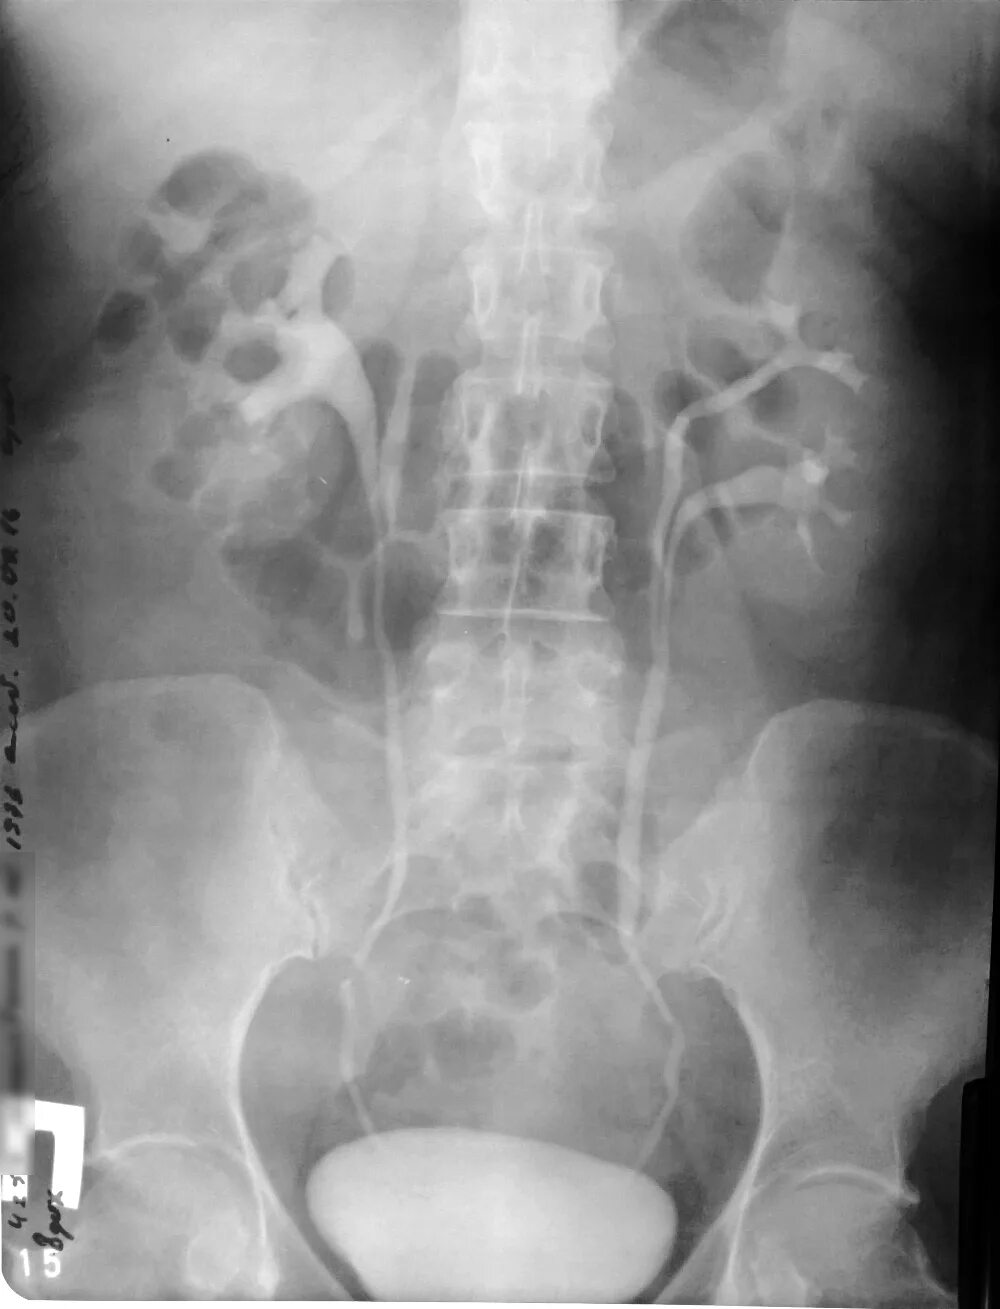

Как делается урография